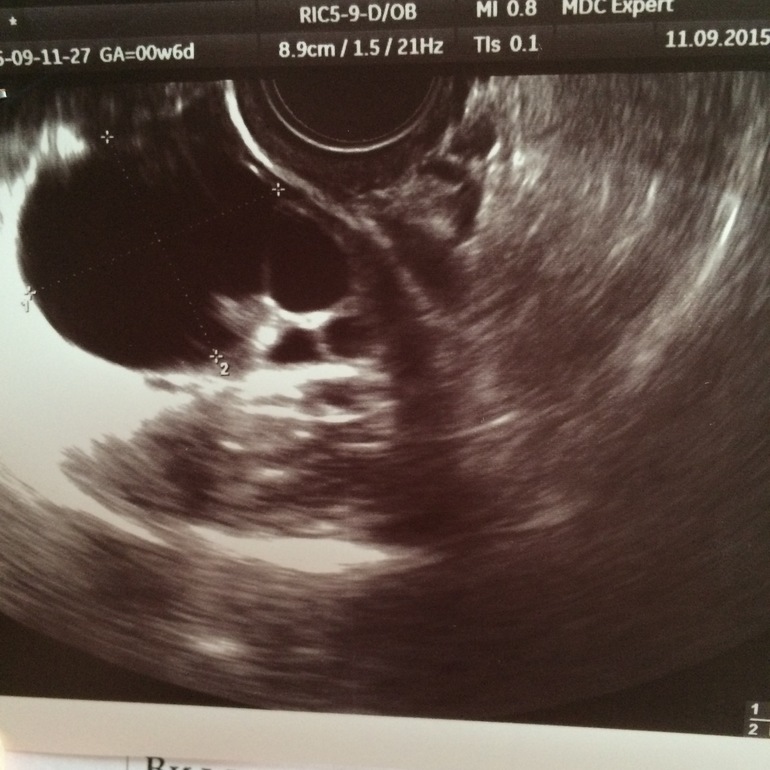

ФолликулометрияЗдравствуйте!уже который месяц киста не проходит,пила дюф и джес,сейчас сдала анализ на онкомаркеры посмотрим что будет,есть шанс что она на гормонах рассосется?фото подкат

с июня точно она есть до этого не знаю может и раньше образовалась,мне хотят на 3-4 месяца назначить гормоны говорят что должна уйти, вчера врачиха осматривала наковыряла,что я ее второй день ощущаю(кисту) боюсь что лопнет или перекрутится,не дермоидная точно, узистка сказала вряд ли эндометриоидная,остается фолликулярная